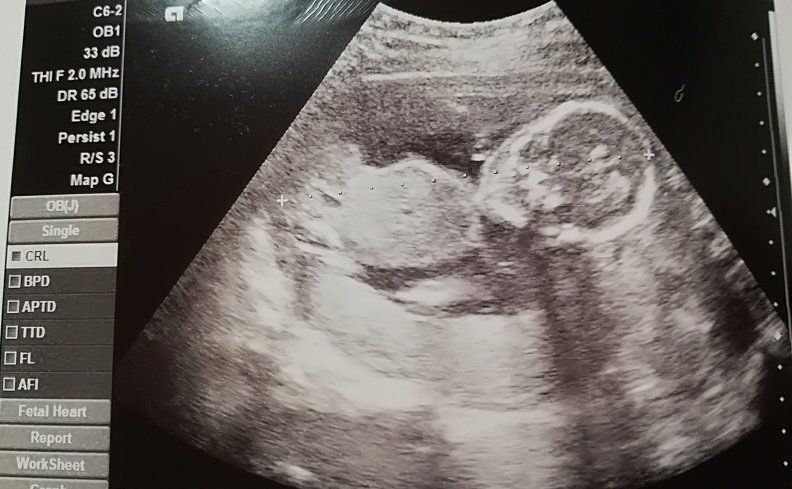

妊娠9週目のエコー写真

「もう、人の形をしている!」と驚きました。妊娠と同時に、里帰り先の産院を予約しました。その喜びをすべて吹っ飛ばしたのが、“つわり”。程度は違うものの皆さん経験するようですが、私は、家のビニール袋がすべてなくなるまで吐いてしまうという重症でした。内科で毎日点滴を受けながら乗り切り「母が食べられなくても、赤ちゃんて育つものだなぁ」と、感心しながら健診を受けていました。